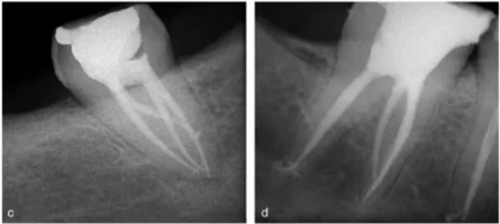

使用手術(shù)顯微鏡是非常有幫助的,特別是在那些根管口被鈣化物覆蓋的病例中,這些鈣化物可以使用超聲尖或長柄小球鉆輕松去除(圖 14a-d)。